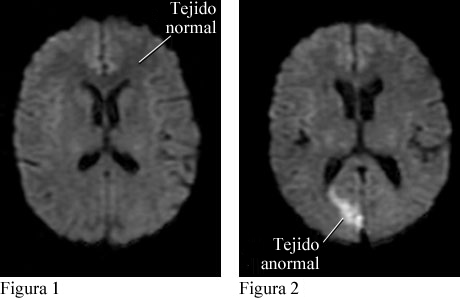

Cortesía de Intermountain Medical Imaging, Boise, Idaho. Todos los derechos reservados.

La figura 1 es una vista superior del cerebro que muestra tejido normal. La figura 2 es una vista similar que muestra tejido anormal causado por un ataque cerebral.